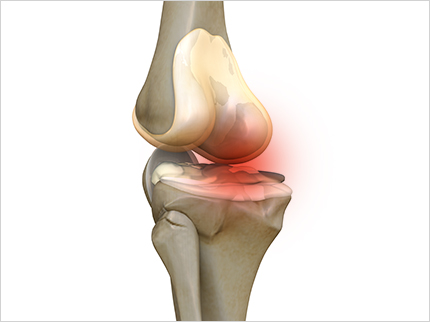

콘드로이친 효능 2. 통증과 염증 감소

관절 속 충격완화 및 충격을 방지하는 역할을 하는 콘드로이친 성분으로 하여금 연골 형태 및 탄력을 유지시킴으로 통증은 완화시키고 염증은 억제하는데 도움이 됩니다. 연구 결과 통증 완화 감소 정도가 소염진통제 만큼 뛰어난 것으로 알려져 있습니다.